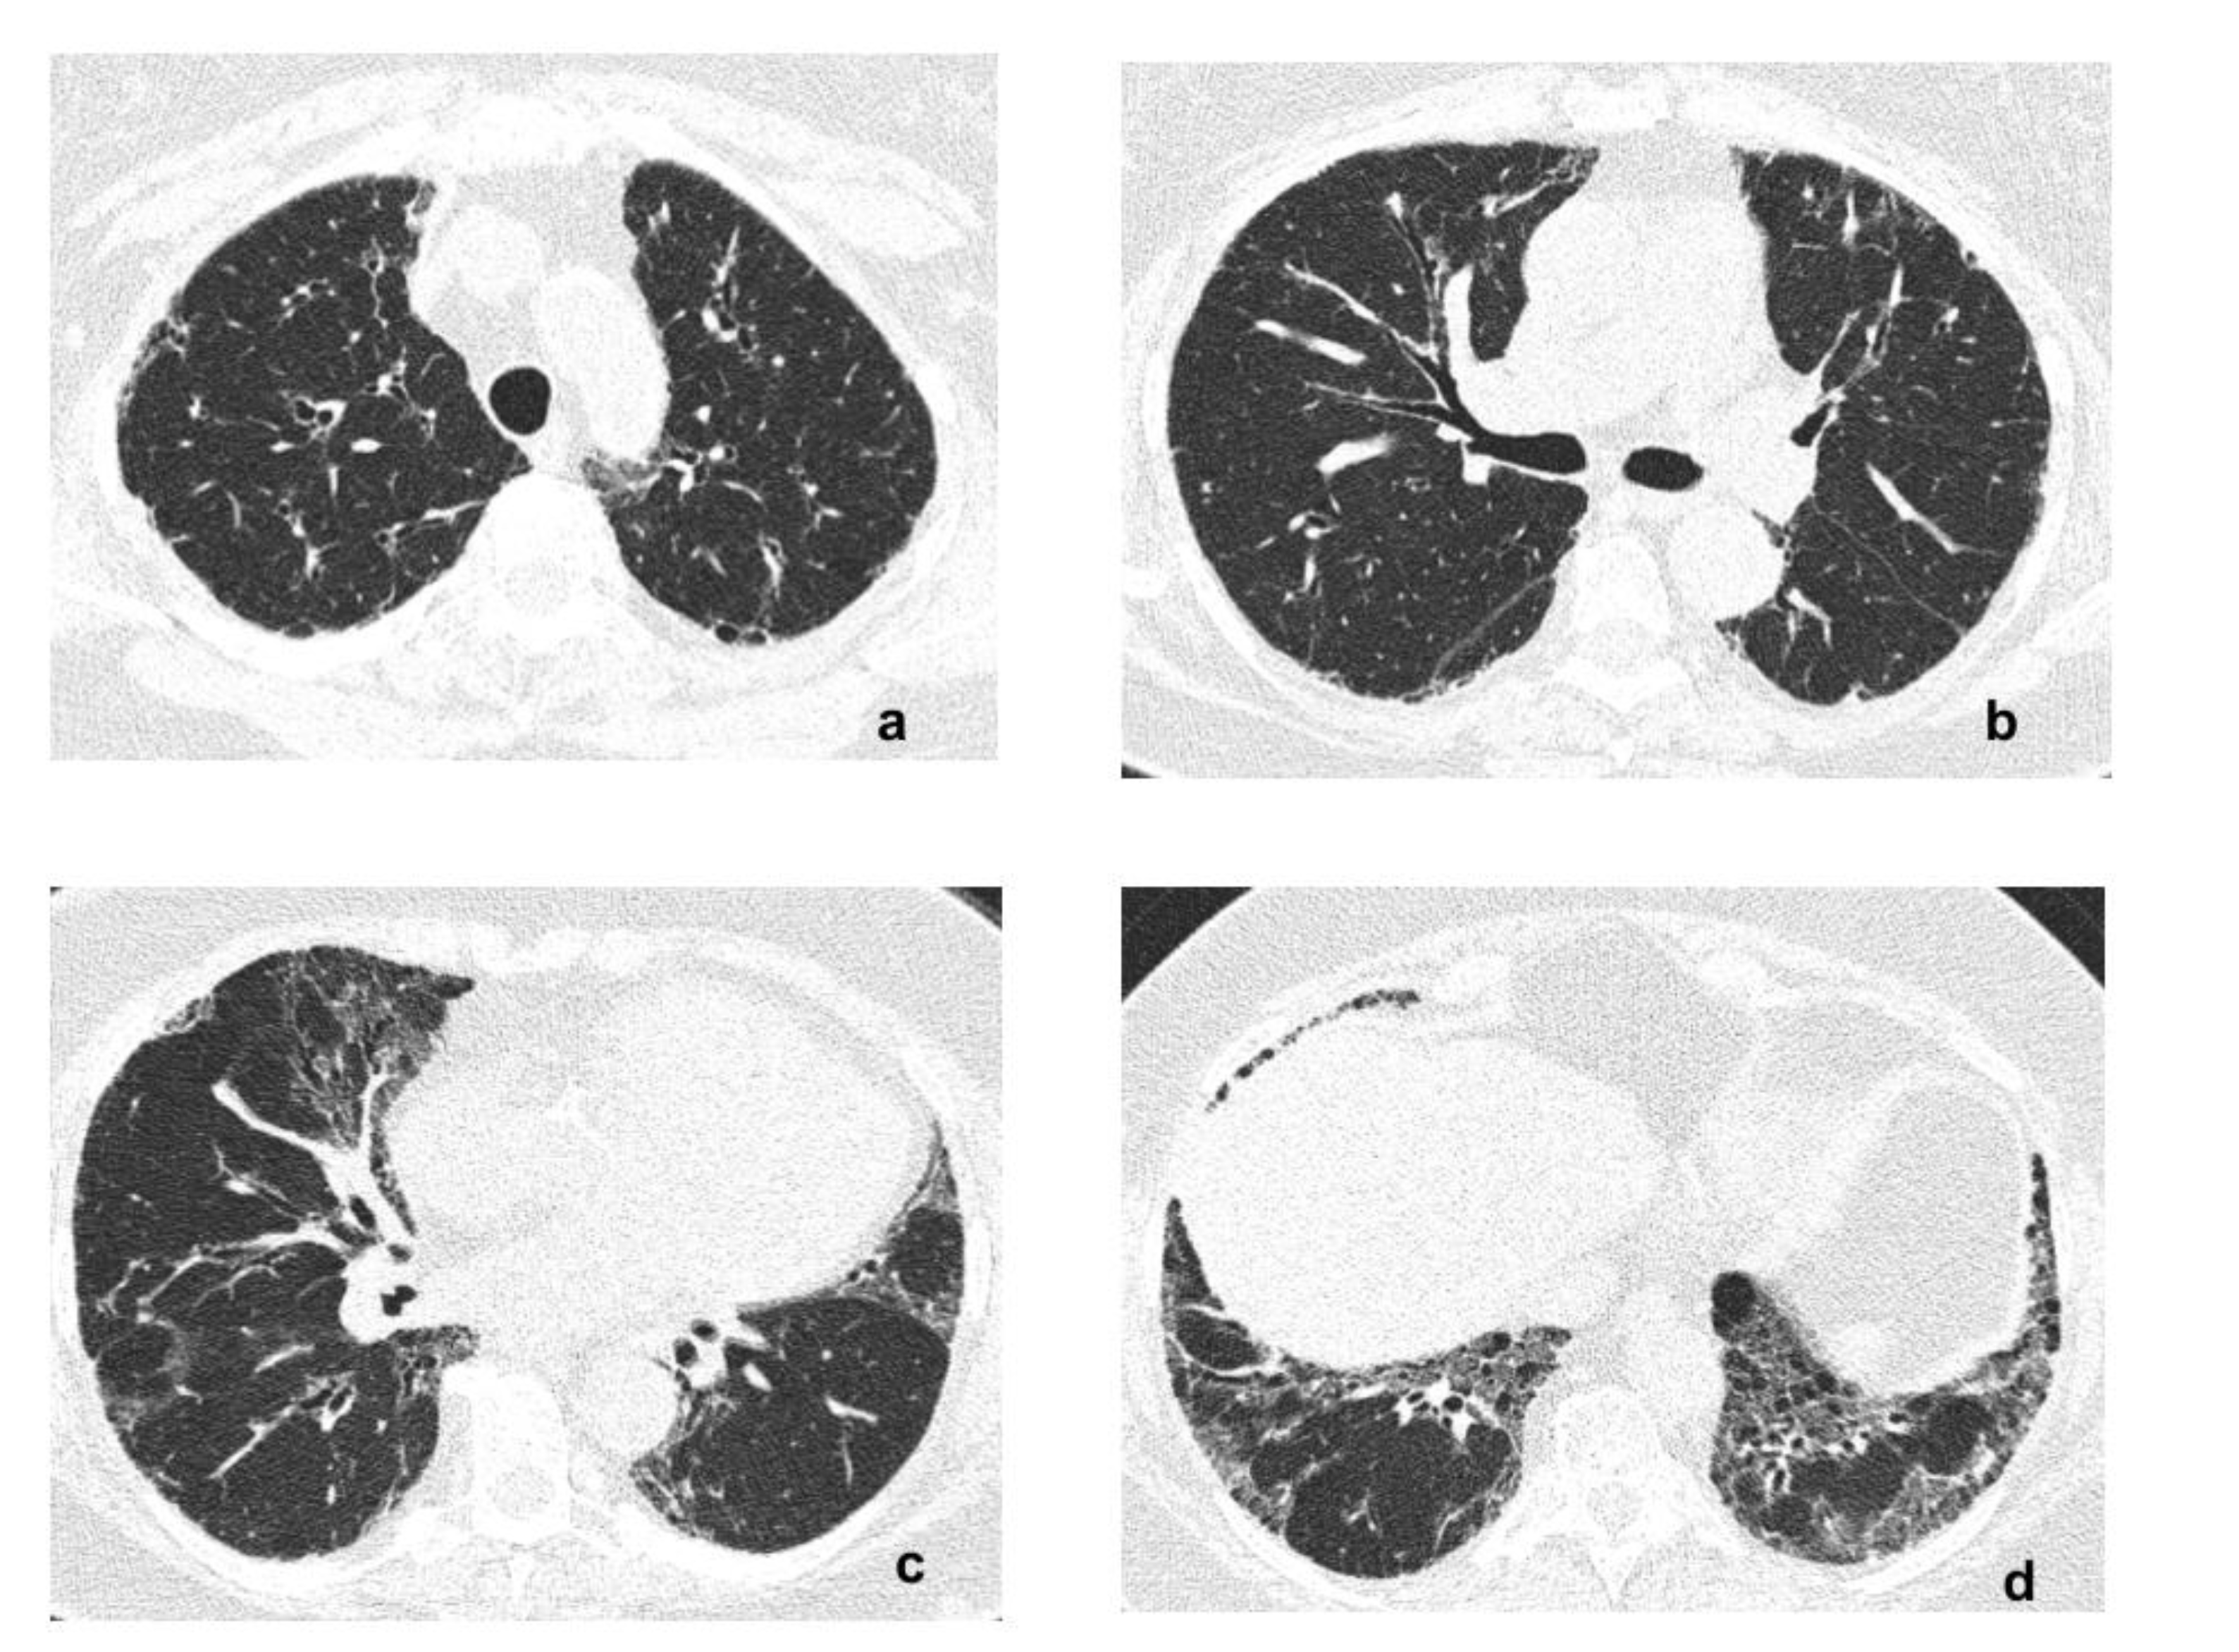

2. Case Report